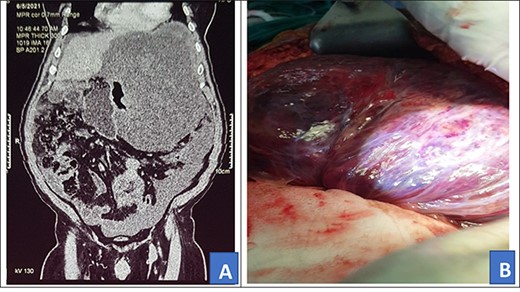

A 46-year-old African male was admitted with history of progressive weight loss and abdominal distension for 7 months. He had no history of abdominal pain, diarrhea of constipation. He, however, reported a history of on-and-off evening fevers. In review of systems, he had a history of swelling of left lower limb and had been on tabs rivaroxaban 20 mg once daily as treatment for deep venous thrombosis diagnosed 5 months prior. Rivaroxaban was stopped 24 hours prior to surgery and then continued post-operatively to complete 6 months of treatment. On examination, he had gross abdominal distension with a firm mass arising from the left lower quadrant. He also had swelling of the left lower limb with darkening of the overlying skin. Other systemic examinations we unremarkable. Prior to admission, he had done an abdominal CT scan that showed a huge mixed density soft tissue intra-abdominal mass exerting pressure on surrounding viscera (Fig. 3A). Fibrosarcoma diagnosis had been confirmed by US-guided biopsy and histology. The patient received neo-adjuvant chemotherapy, intravenous doxorubicin 100 mg with intravenous mesna 1000 mg in 100 ml of normal saline and intravenous ifosfamide 9500 mg in 3 l of normal saline with intravenous mesna 2375 mg in 1 l of normal saline every 21 days, four cycles of chemotherapy prior to referral for surgery. Investigations, including complete blood count, renal function tests, liver function tests and prothrombin time, were all grossly normal and the patient was scheduled for cytoreductive tumor resection.

Intra-operatively, a giant 40 × 35 × 12 cm liposarcoma measuring 10.1 kg was found involving the left ureter (Fig. 3B). The transverse colon, descending colon and sigmoid colon were attached to the anterior part of the mass and the rectum was displaced to the right. Other abdominal viscera were normal. The mass was mobilized from the colon. The entire mass en bloc, including the left ureter, were excised (Fig. 4). Then, the left to right ureteroureterostomy with a Double-J stent insertion done.

Preoperative abdominal CT scan (A) and intra-operative picture (B) for Patient 3.